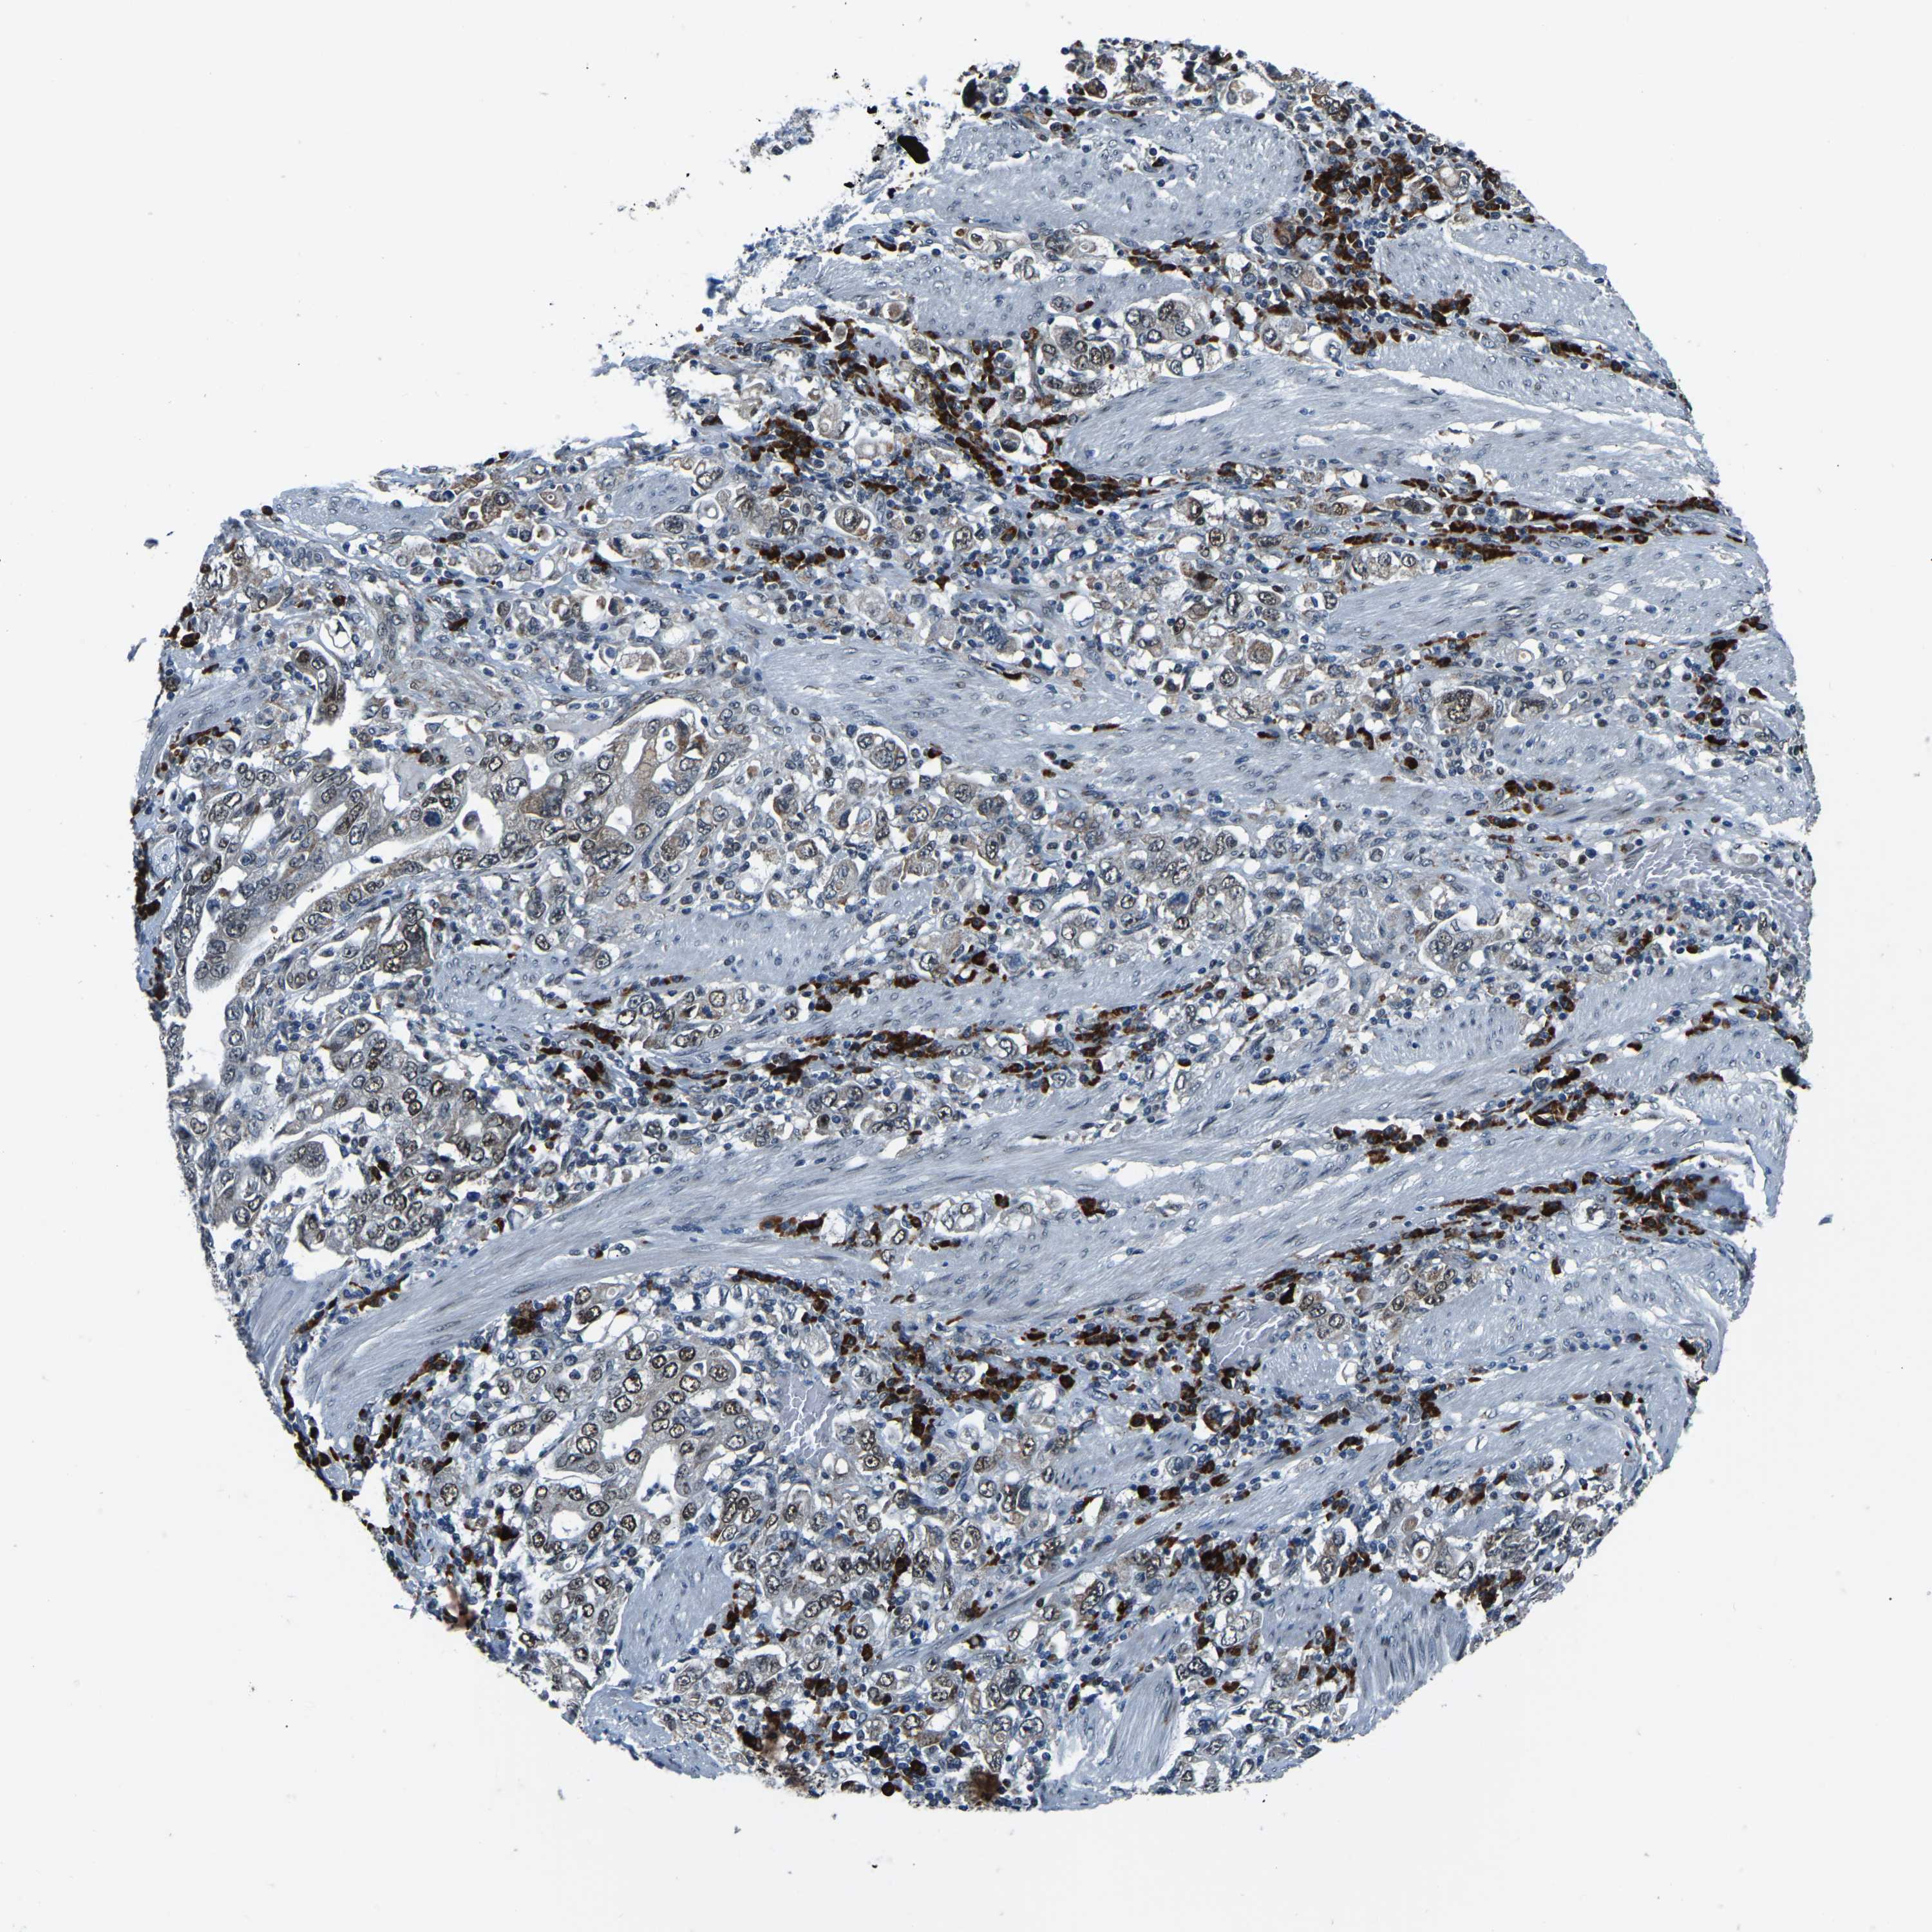

STOMACH CANCER - Protein expressioni

A mouse-over function shows sample information and annotation data. Click on an image to view it in a full screen mode. Samples can be filtered based on level of antibody staining by selecting one or several of the following categories: high, medium, low and not detected. The assay and annotation is described here.

Note that samples used for immunohistochemistry by the Human Protein Atlas do not correspond to samples in the TCGA dataset.

Antibody stainingi

Antibody staining in the annotated cell types in the current human tissue is reported as not detected, low, medium, or high, based on conventional immunohistochemistry profiling in selected tissues. This score is based on the combination of the staining intensity and fraction of stained cells.

Each image is clickable and will lead to virtual microscopy that enables deeper exploration of all samples and also displays staining intensity scores, fraction scores and subcellular localization as well as patient and tissue information for each sample.

Antibody HPA019486

Antibody HPA021517

Staining

High

Medium

Low

Not detected

Intensity

Strong

Moderate

Weak

Negative

Quantity

>75%

75%-25%

<25%

None

Location

Nuclear

Cytoplasmic/membranous

Cytoplasmic/membranous,nuclear

Adenocarcinoma, NOS